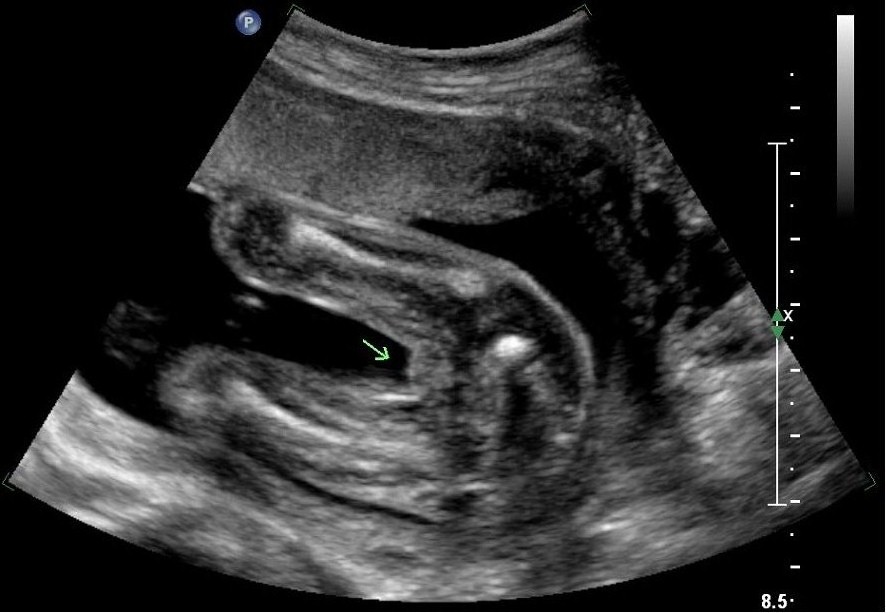

These are my 2 potty shots from my 20 week ultrasound ... Anyone willing to guess?

Not great on potty shots but bottom one looks pretty girly maybe:)

At 20weeks if it was a boy, I would expect to see more of a 'protusion', but then again, some boys are very good at hiding their bits.....I am hesitantly guessing girl...

I think these shots are ambiguous unfortunately.

I can't really tell. I don't see labia or scrotum. So it's kinda a 50-50 from me. I think the lower shot is taken too far back to show. The upper one the legs are super-close together. Sorry!

Thanks for guessing ... The confusion is that at my 19 week scan I saw & was told boy, then at my 20 week scan i was again told boy but a second tech said girl because she wasn't seeing any boy parts when she looked ...

Personally I cannot see any detailed gender parts in my pictures! :)